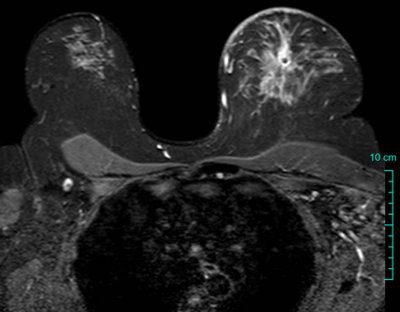

| To maintain consistency in breast MRI, it's important to position patients properly and instruct them to remain still. A little communication goes a long way toward ensuring image quality. Proper protocol selection allows visualization of breast parenchyma, skin, axillae, and other structures as seen on this axial T2-weighted image. Image courtesy of Dr. Mark Lawton, Wheaton Franciscan Healthcare, Milwaukee. |